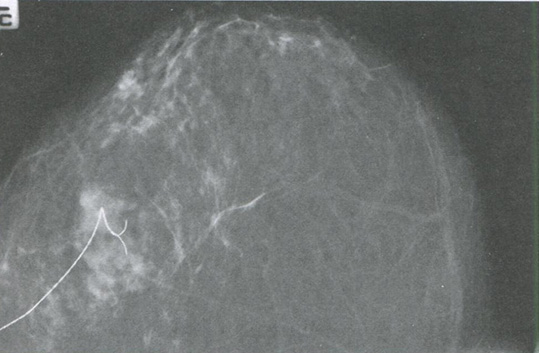

- выполнение предоперационной внутритканевой маркировки непальпируемых образований (рис. 3.5);

Рис. 3.5. Предоперационная внутритканевая маркировка непальпируемого образования